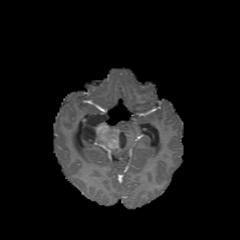

Deep Active Lesion Segmentation

[45]: Lesion segmentation is an important problem in computer-assisted diagnosis that remains challenging due to the prevalence of low contrast, irregular boundaries that are unamenable to shape priors. We introduce Deep Active Lesion Segmentation (DALS), a fully automated segmentation framework that leverages the powerful nonlinear feature extraction abilities of FCNs and the precise boundary delineation abilities of ACMs. Our DALS framework benefits from an improved level-set ACM formulation with a per-pixel-parameterized energy functional and a novel multiscale encoder-decoder CNN that learns an initialization probability map along with parameter maps for the ACM. We evaluate our lesion segmentation model on a new Multiorgan Lesion Segmentation (MLS) dataset that contains images of various organs, including brain, liver, and lung, across different imaging modalities—MR and CT. Our results demonstrate favorable performance compared to competing methods, especially for small training datasets. -